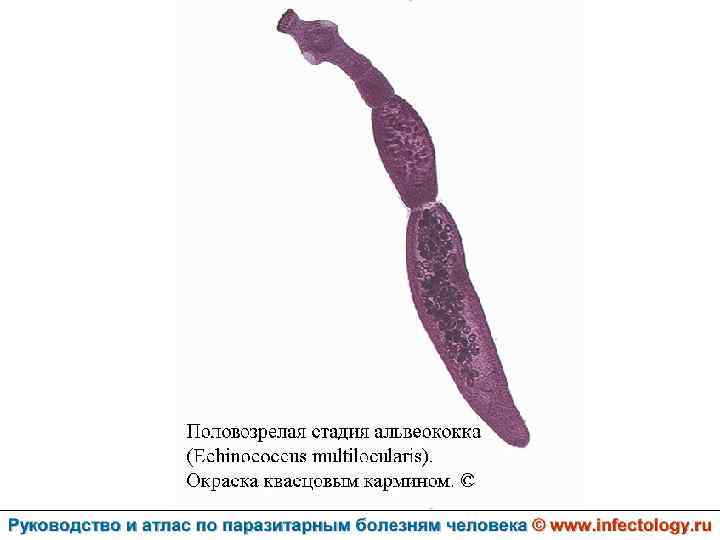

Альвеолярный (многокамерный) эхинококкоз человека (альвеолярный гидатидоз) (шифр по МКБ 10 - B 67. 5 -7) – зоонозный биогельминтоз, характеризующийся чрезвычайно тяжелым хроническим течением, первичным опухолевидным поражением печени, нередко с метастазами в головной мозг и легкие, а также во многие другие органы. Заболевание часто заканчивается летально.